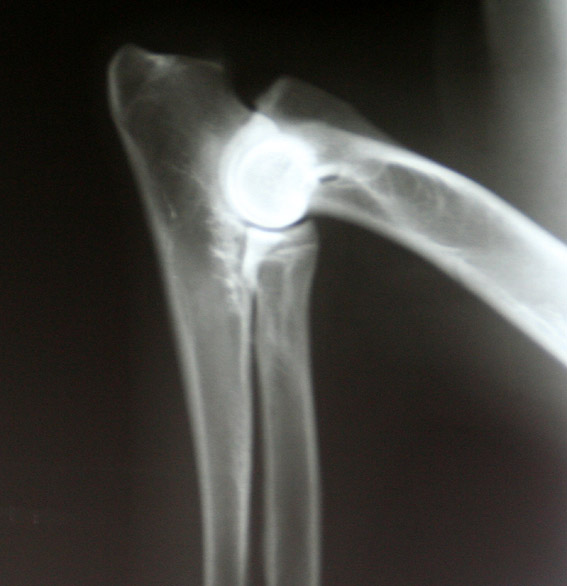

Elleboogdysplasie (ED)

Dit is een verzamelnaam voor verschillende erfelijke ontwikkelingsstoornissen van het ellebooggewricht.

Hieronder vallen bijvoorbeeld: LPA, LPC, OCD en incongruentie van het gewricht. Bij de eerste 3 afkortingen is er sprake van een los fragment in het gewricht. Het kan dan gaan om een botfragment (Los Processus Anconeus, Los Processus Coronoideus) of een kraakbeenfragment (OsteoChondrosis Dissecans). Bij de bovengenoemde term ‘incongruentie’ gaat het om een ongelijkheid; een niet goed passen van de gewrichtsvlakken.